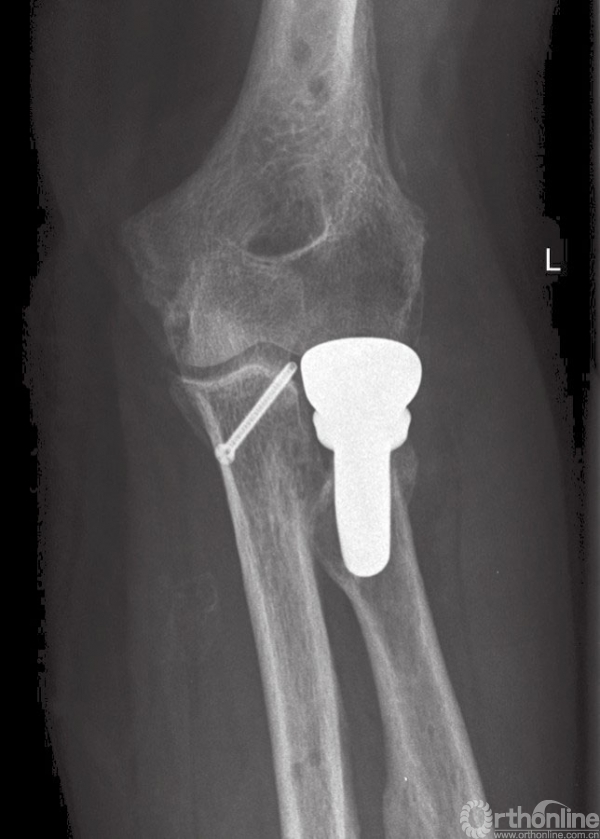

图10 长期随访患者,正位片显示桡骨头假体位置满意,伴有少量异位骨化

图11 长期随访患者,侧位片显示关节复位满意